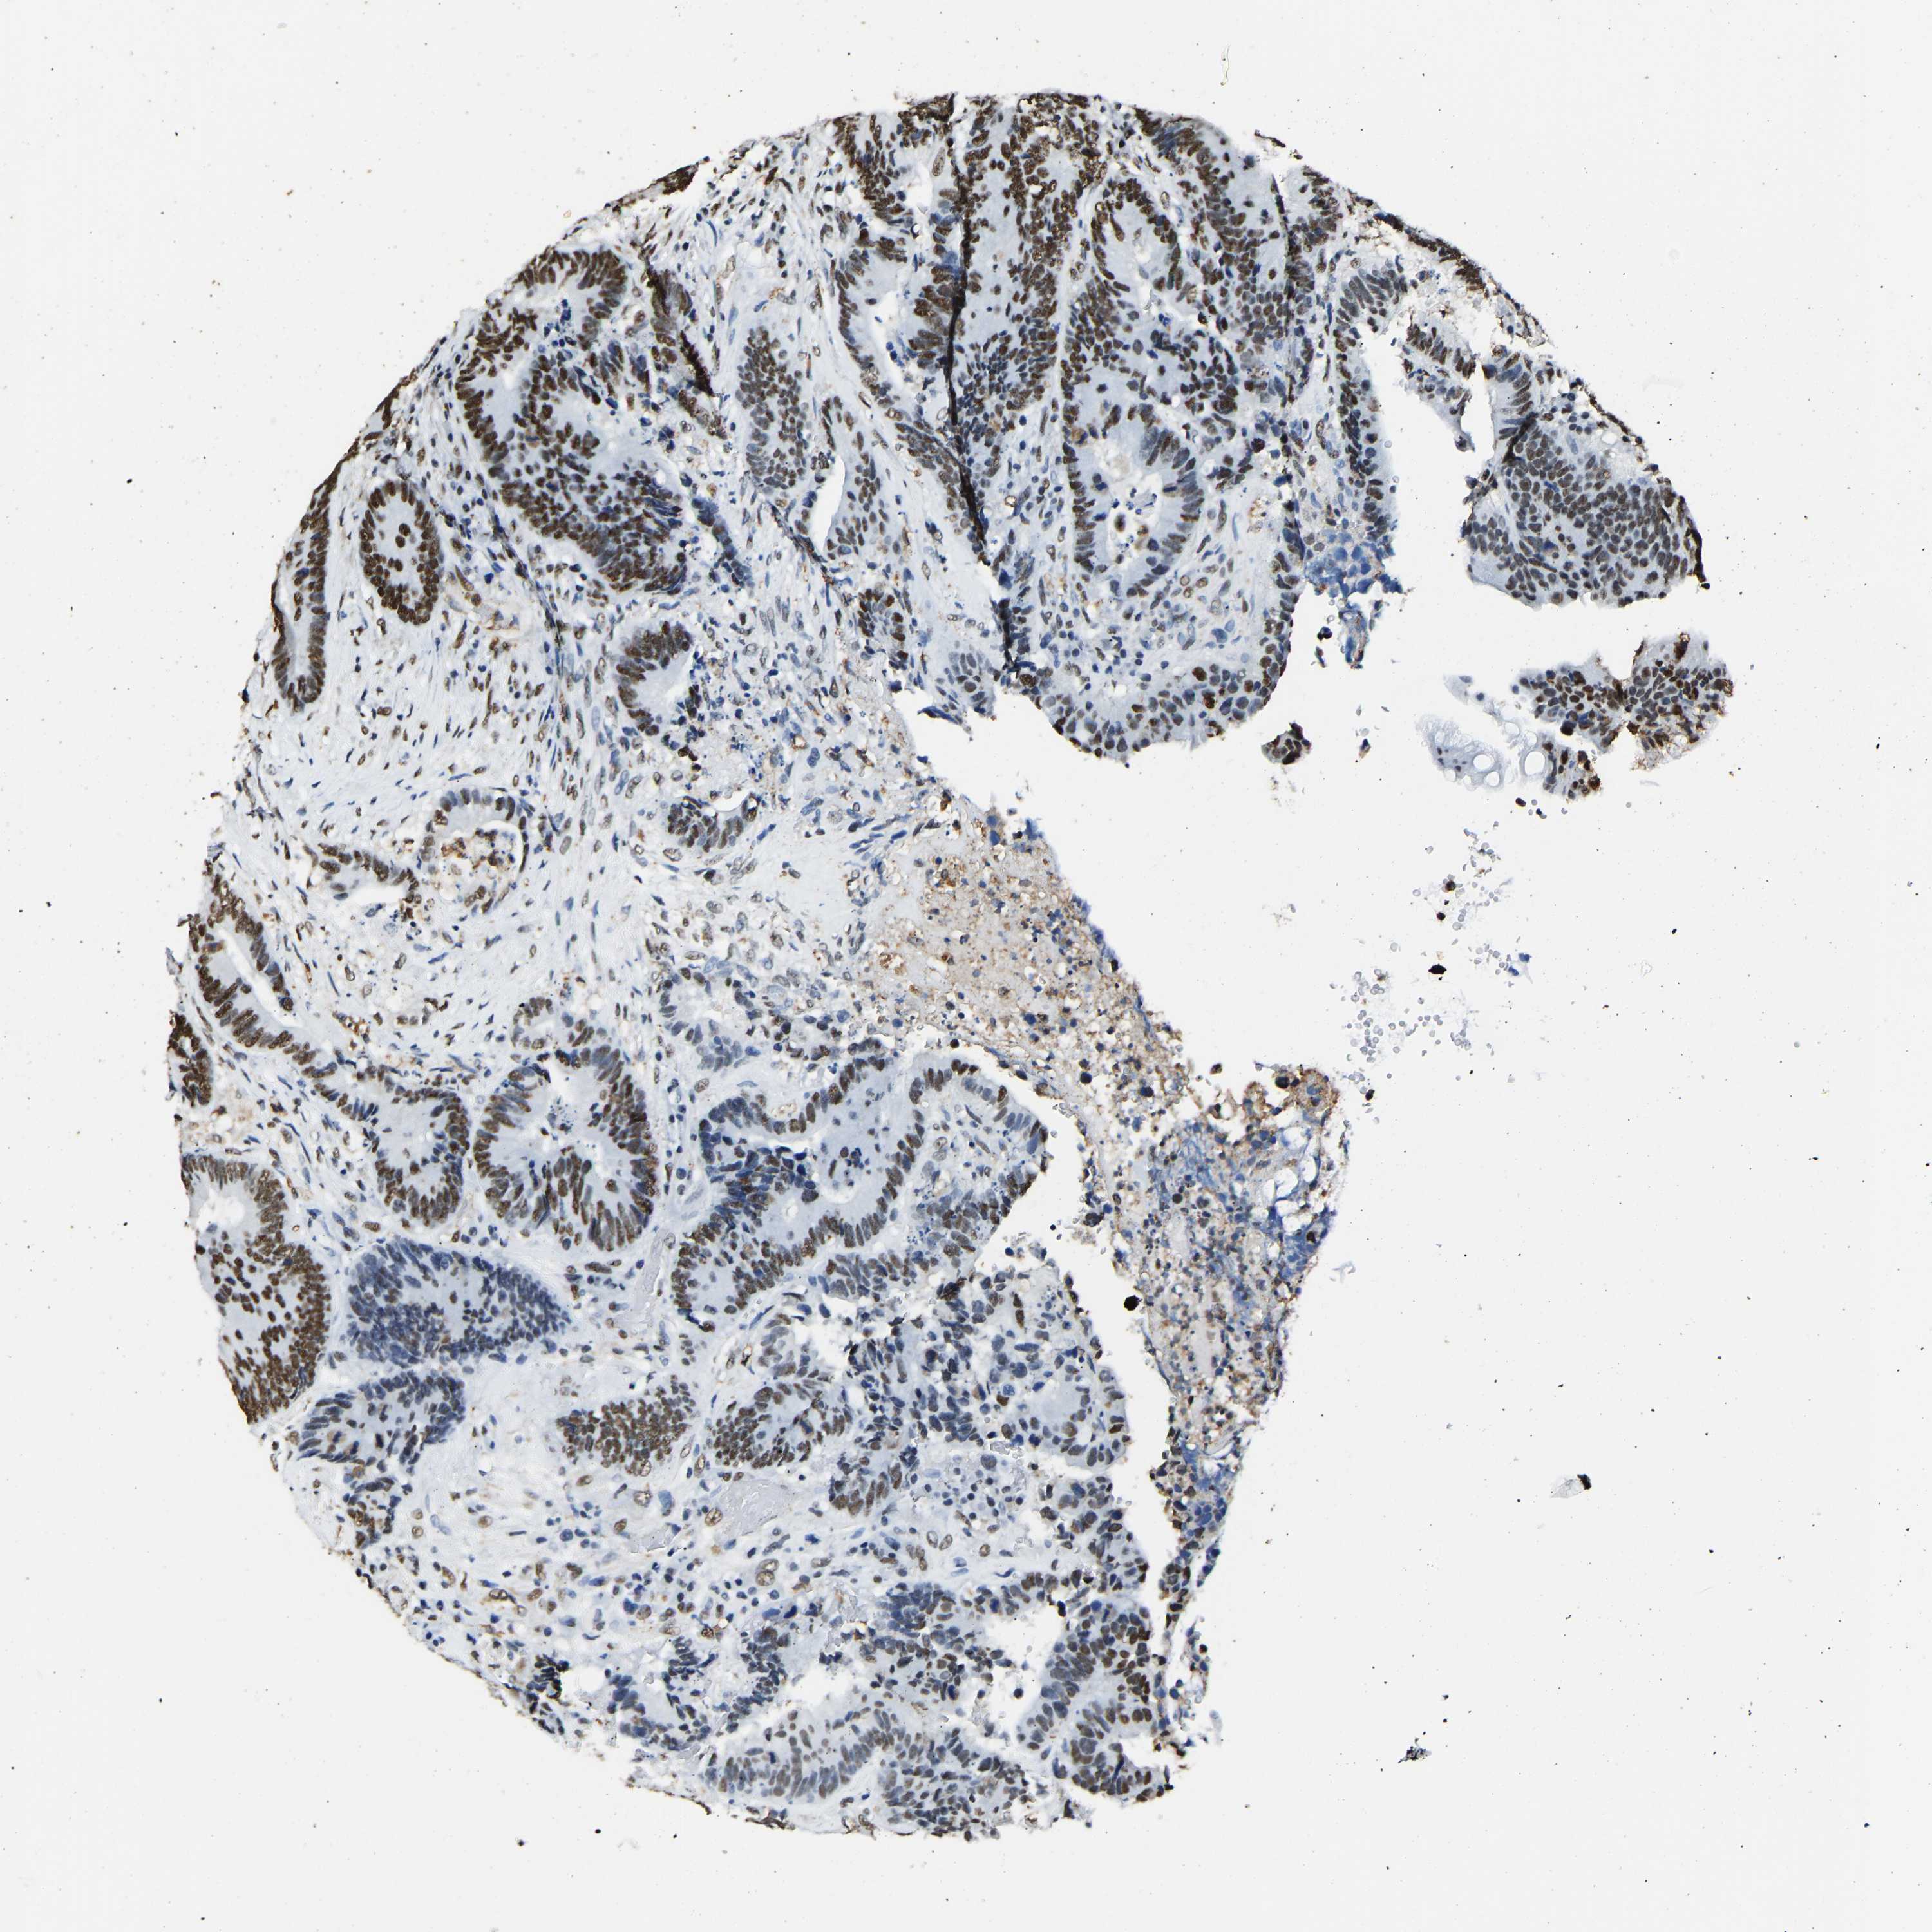

CANCER COLORECTAL CANCER Show tissue menu

Colorectal cancer

Human cancer